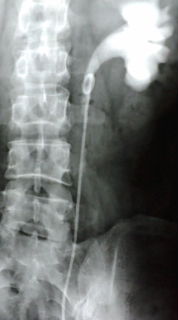

朝10時、病院で腎臓から膀胱までの造影剤による撮影。

撮影では、大きな石はほとんどなくなっていた。

←造影剤の影

←石

←造影剤の影(腎臓)

←石がなくなってる

←ステント付近に小さい石

この石が出てきたのだ!